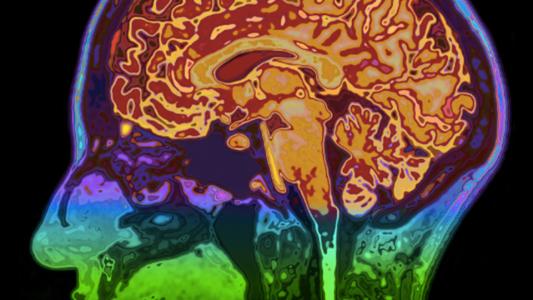

Neuroscientists want to beam experiences directly into your brain

It's a breakthrough for the blind and paralyzed, not the first step toward the Matrix. (Promise.)

The eternal sunshine of the stressed out mind

Researchers at Cambridge University have finally figured out how the brain stops stressful thoughts and memories...

A prosthetic memory can help you remember

Scientists have figured out how to hack the brain's memory.